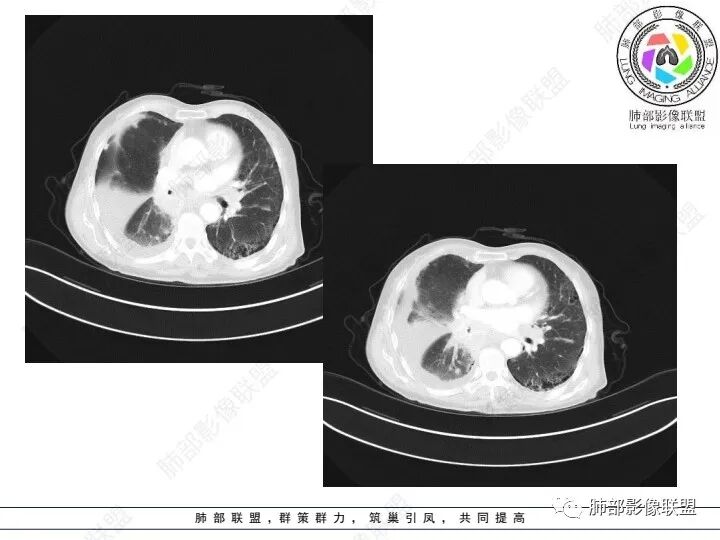

老年女性,肺气肿背景。腹痛、便血入院。右肺下叶脊柱旁软组织肿块,强化不均匀,中心有坏死,纵隔及双侧肺门多发肿大淋巴结、有融合,右下支气管周围为主,包绕支气管生长,且管壁增厚伴环形钙化、狭窄,增强后有环形强化。右侧胸膜见结节灶,增强后明显强化;右侧胸腔积液。考虑:右下肺恶性肿瘤伴纵隔、肺门多发肿大淋巴结,胸膜转移,低分化腺癌?Ca125明显升高,老年女性 是否有妇科恶性肿瘤?黏液腺癌 肺内、纵隔转移?

双肺间质性改变,右肺下叶支气管环形增厚,支气管变窄,周围见钙化影,右肺下叶软组织占位,明显的坏死,明显环形强化,两侧肺门及气管隆突下淋巴结肿大。右侧胸腔积液,肝脏周围少量腹腔积液,老年女性患者腹痛便血,Ca125明显增高。考虑1一元论:腹腔恶性肿瘤(胃肠道或卵巢来源)肺内及胸膜腹膜转移;2二元论:右下肺粘液表皮样癌/腺样囊性癌,腹腔胃肠道或卵巢来源肿瘤。

女,69,腹痛、便血4小时。CA125增高。胸部CT:肺气肿背景。右下叶不规则肿块影,处于外周气肿带与正常肺交界区,强化不均匀,中心有坏死;纵隔及肺门多发肿大淋巴结、融合,包绕支气管,部分钙化、环形强化;右下支气管周围管壁增厚伴环形钙化、狭窄。右侧胸膜多发结节灶,增强后明显强化,右侧胸腔积液。考虑恶性,右下肺腺Ca多发转移?转移瘤?鉴别TB、IgG4等。

右下肺肿块,其内坏死边界不清,边缘轻度强化,可见引流支气管,管壁增厚,冰冻肺门,内见斑点状钙化,中间支气管变窄呈针孔样,可见环状强化及血管浸蚀,右侧积液,间隔旁型肺气肿,慢阻肺背景,综和考虑腺并肺门纵隔及胸膜转移,纵隔内淋巴结环状强化,血管破坏显著,肿大淋巴结内多发钙化,引流支气管壁增厚,鉴别一下TB

3、胸部增强CT示右肺下叶脊柱旁不规则软组织肿块,侵及壁层胸膜外,密度不均匀,不均匀强化,中心低密区可疑坏死,右侧胸腔积液、胸膜结节影或结节样增厚,增强扫描可见强化,右侧肺门及纵隔内可见淋巴结肿大、融合,右侧中尖段支气管及右肺下叶支气管受侵,管腔狭窄。